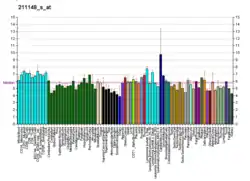

Angiopoietin-2 is a protein that in humans is encoded by the ANGPT2 gene.[5]

- 1 2 3 GRCh38: Ensembl release 89: ENSG00000091879 - Ensembl, May 2017

- 1 2 3 GRCm38: Ensembl release 89: ENSMUSG00000031465 - Ensembl, May 2017